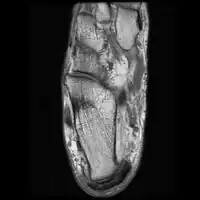

Medical imaging

Ultrasound imaging can be used to evaluate tissue strain, as well as other mechanical properties.[31]

Ultrasound-based techniques are becoming more popular because of its affordability, safety, and speed. Ultrasound can be used for imaging tissues, and the sound waves can also provide information about the mechanical state of the tissue.[32]

Achilles tendinopathy

Achilles tendinopathy and peritendonitis